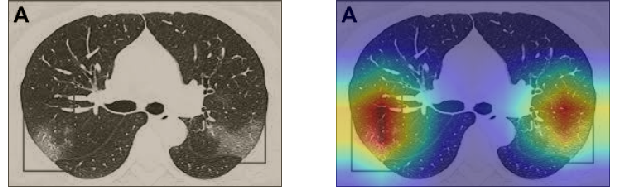

To understand how the deep neural networks represent the CT images in the high-dimensional feature space we apply the t-SNE algorithm to visualize these features. For each image in the SARS-CoV-2 dataset we first extract the 2048-dimensional feature vector from the penultimate layer of the Inception V3 model. Next, we apply t-SNE to map the features on to 2D space and then visualize the embeddings of training and test representations. Figure 11 clearly shows two well-separated clusters of the CT images of COVID-19 and Non-COVID-19. This indicates that the distribution of training and test features are quite similar to each other, which indicates good generalization capabilities of our model. The clear and wide margin between the two classes shows how nicely the CT images are separated in feature space.

We also repeat the same procedure for the COVID19-CT dataset. The feature vectors are extracted from the penultimate layer of the DenseNet169 model. The length of the feature vectors is 1664 dimensions. We again apply t-SNE to map the features on to 2D space to explore and visualize them. Figure 12 shows two clusters representing CT images for the COVID-19 and Non-COVID-19 classes. Even though the classes are fairly distinguishable with a clear decision boundary, however, we can see that some CT images are misclassified, and more specifically the Non-COVID-19 CT images from the test set.